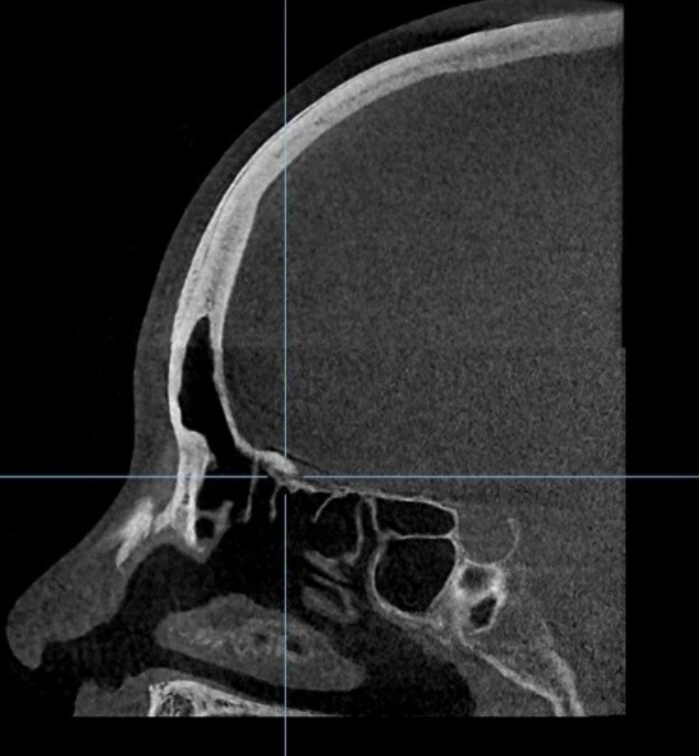

10년전 수술한 메틸본드 이마 성형 씨티사진 입니다.

0사진에서 보신것처럼 메틸본드를 제거하고 거상술을 받아도 눈썹위로?? 저런 볼륨이나

형태가 생기나요?? 아니면 메틸본드로 인한 것인지 궁금합니다.

메틸본드 제거 후 이마거상을 해도 부자연스러운 이마 곡선이 생기는지 ㅠㅜ 너무나 궁금합니다.